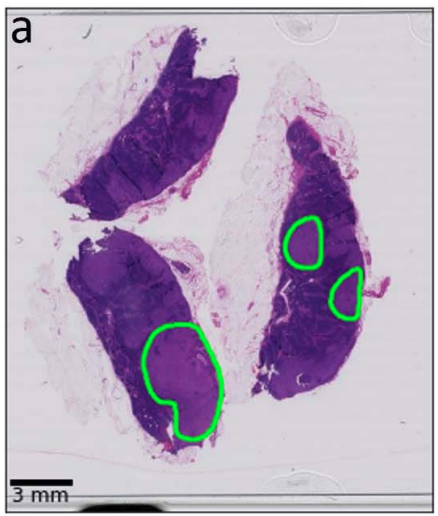

Tools in Digital Pathology

tumor

non tumor

Can we refine these automatically?

false positives

false negatives

• Training on a single slide

necrotic tumor

viable tumor

non-tumor

Manual coarse annotation

Computational refinement

Ground truth